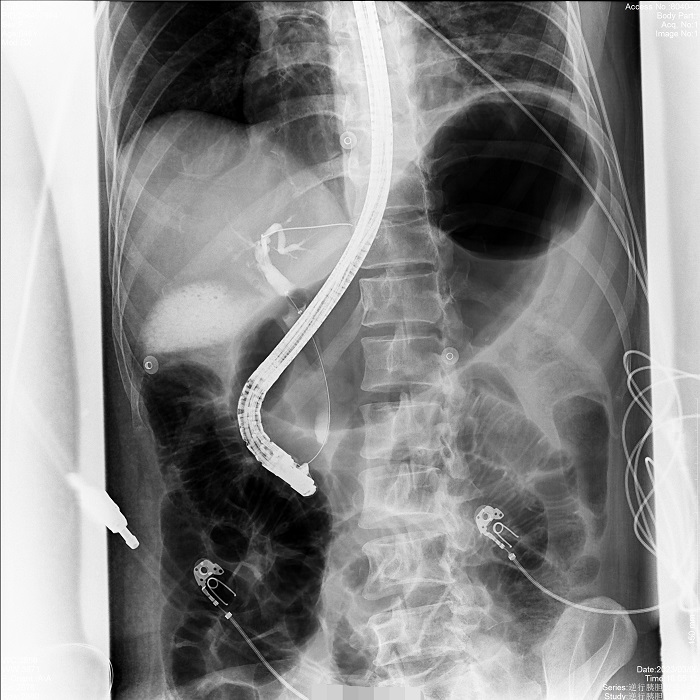

病例2:患者間歇性上腹部脹痛不適2年,MRCP示膽總管明顯擴(kuò)張,膽囊多發(fā)結(jié)石,醫(yī)生決定應(yīng)用ERCP的手術(shù)方式解除膽道梗阻,通暢引流。在普利德多動(dòng)能動(dòng)態(tài)平板DRF上進(jìn)行ERCP應(yīng)用,成功取出全部結(jié)石,術(shù)后觀察膽汁引流通暢,患者病情平穩(wěn)。